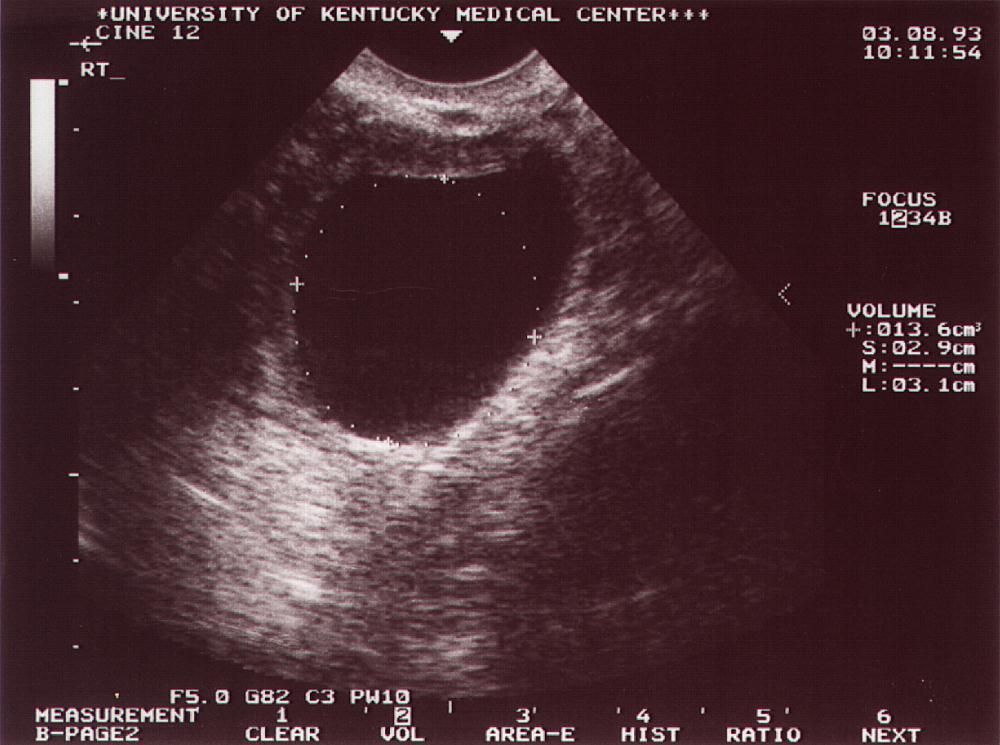

| Age at Dx |

42 |

| CA-125, U/ml |

14 |

| Physical Exam |

Palpable |

| TVS size, cm3 |

14.7 |

| Tumor Stage |

IA |

| Treatment |

S |

| Status |

A & W |

| DX Date |

Mar-93 |